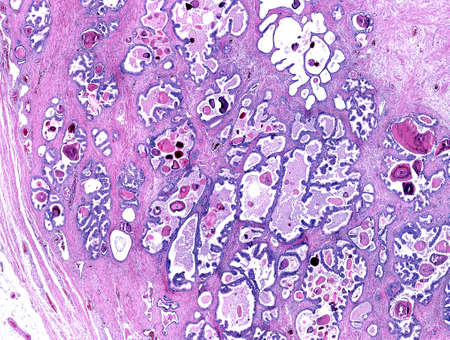

Low magnification of a human prostate gland in a 70-year-old man. The prostate gland appears with dilated alveoli, which contains many corpora amylacea (prostatic concretions) in their lumen. Light microscope micrograph. Hematoxylin & eosin stain.